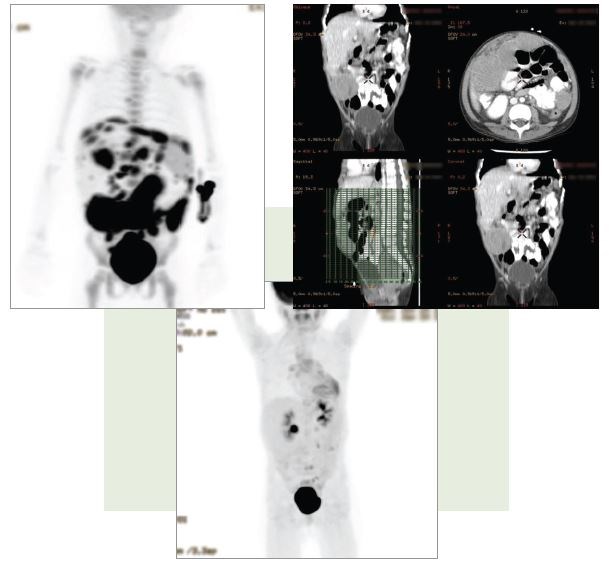

An additional patient we enrolled in the trial was a young child who was on hospice when I first saw her. You can see on the positron emission tomography scan (Figure 3) that the patient had an enormous amount of disease. After 15 hours of surgery, we were able to eliminate all of her disease, and she is alive and well now in the eighth grade.

FIGURE 3. “INOPERABLE” TUMORS IN A YOUNG CHILD